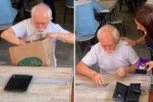

Foto: pixabay.com

Foto: pixabay.com